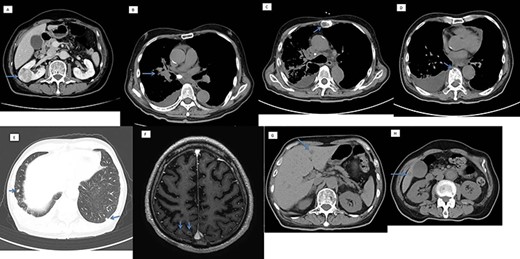

On computed tomography (CT) scan, there was a 38-mm right renal mass, giving an impression of renal cancer, right hilar lung tumor, and bone, lungs, brain, and, liver metastases, with right pleural effusion (Fig. 1). We wanted to check if the renal mass was a primary renal cell cancer or metastatic; a CT-guided renal biopsy was then planned.

Computed tomography scan showing (A) a 38-mm right renal mass (suspected renal cancer), (B) right hilar lung cancer, with metastasis in the (C and D) bone, (E) lungs, (F) brain and (G) liver.